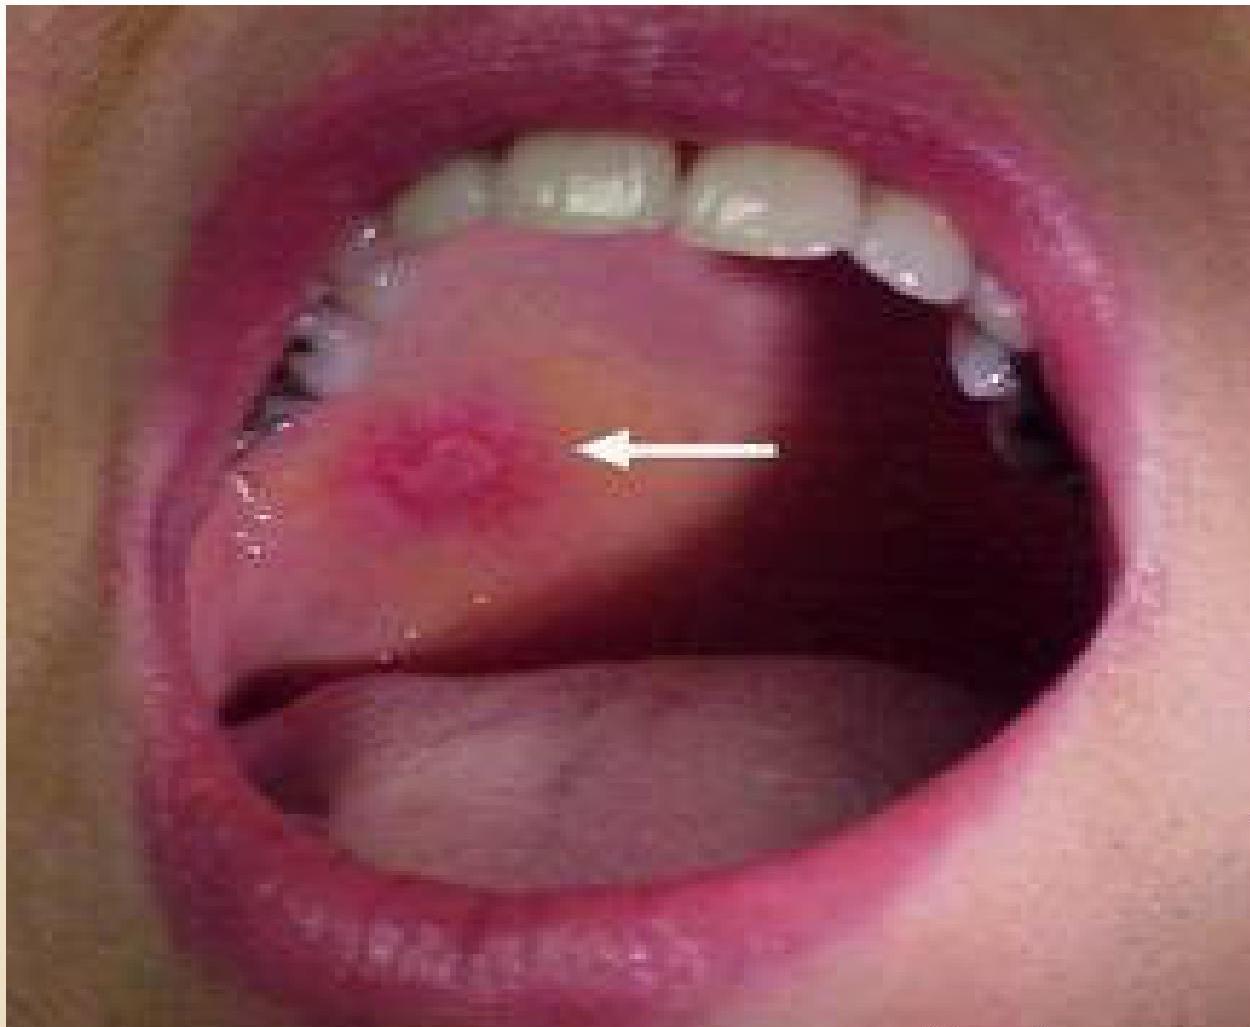

- Discoid Lupus Erythematosus (DLE): (See image)

- Other: Photosensitivity, diffuse maculopapular rash, cutaneous vasculitis, oral/nasal ulcers.

(Left: Discoid Lupus Rash. Right: Malar Rash)

- 6) Mouth: Ulcers

- 7) Skin rash: Skin is affected in 85% patients Butterfly rash Discoid rash Butterfly rash is characteristic of SLE SLE rash gets worse in sunlight (photosensitive)

Sometimes discoid skin lesions are seen

Four SLE criteria are dermatologic:

- Oral ulcerations